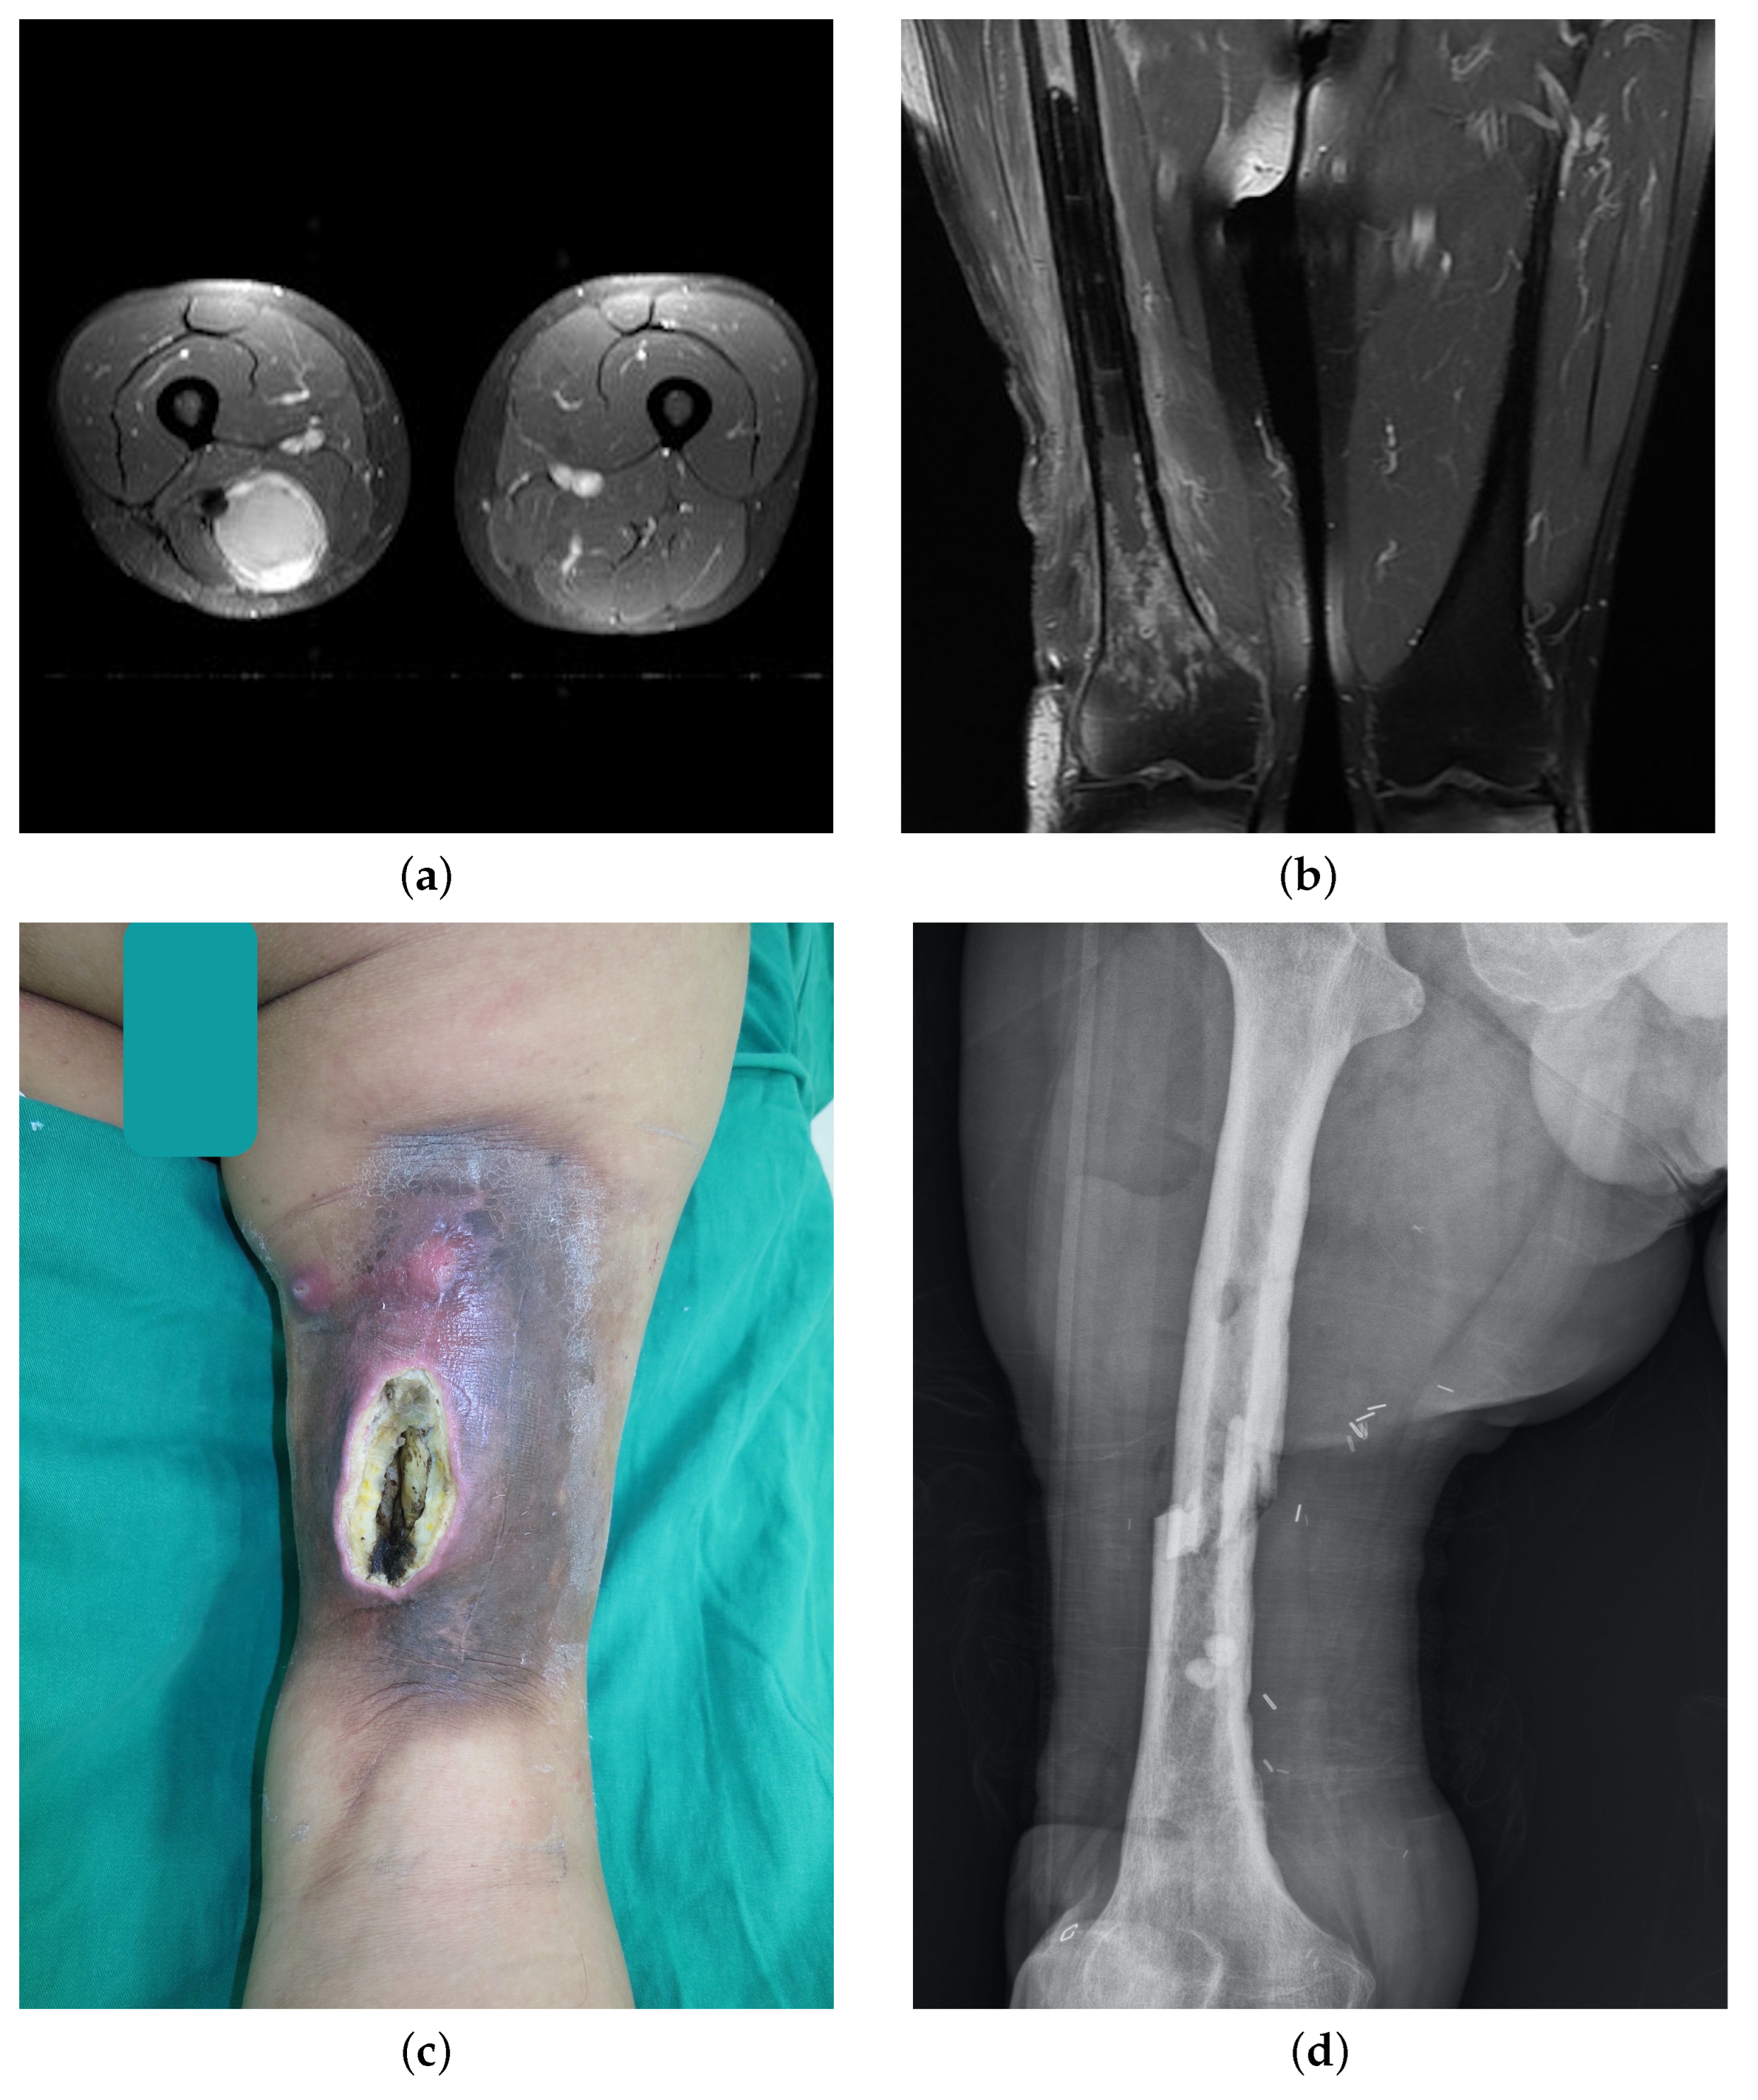

| 1 | M | 76 | Left lower leg | Undifferentiated pleomorphic sarcoma | Positive | 66 | 3 | Chronic ulcers, pathological fracture | Debridement, sequestrectomy, bone graft, ORIF, flap reconstruction | Nonunion bone |

| 2 | F | 69 | Left ankle | Leiomyosarcoma | Positive | 60 | 13 | Chronic ulcers, bone exposure | Debridement, flap reconstruction | Healed wound |

| 3 | F | 26 | Left hip | Undifferentiated pleomorphic sarcoma | Positive | 74 | 67 | Periprosthetic fracture, persistent sinus discharge | Debridement, hip joint arthroplasty, flap reconstruction | No infection sign |

| 4 | M | 36 | Left upper arm | Synovial sarcoma | Positive | 70 | 14 | Persistent sinus discharge, wound poor healing | Debridement, synovectomy | Shoulder disarticulation |

| 5 | M | 45 | Left thigh | Myxoid liposarcoma | Close | 70 | 23 | Persistent sinus discharge, wound poor healing, pathological fracture | Debridement, HBO therapy | AK amputation |

| 6 | F | 57 | Left lower leg | Dedifferentiated liposarcoma | Positive | 70 | 3 | Nonunion bone | Debridement, bone graft, HBO therapy, ORIF, flap reconstruction | BK amputation |

| 7 | M | 48 | Right thigh | Undifferentiated pleomorphic sarcoma | Close | 60 | 36 | Persistent sinus discharge, soft tissue necrosis, nonunion bone | Debridement, sequestrectomy, ORIF, flap reconstruction, pentoxifylline, tocopherol | Bone union, wound healed |